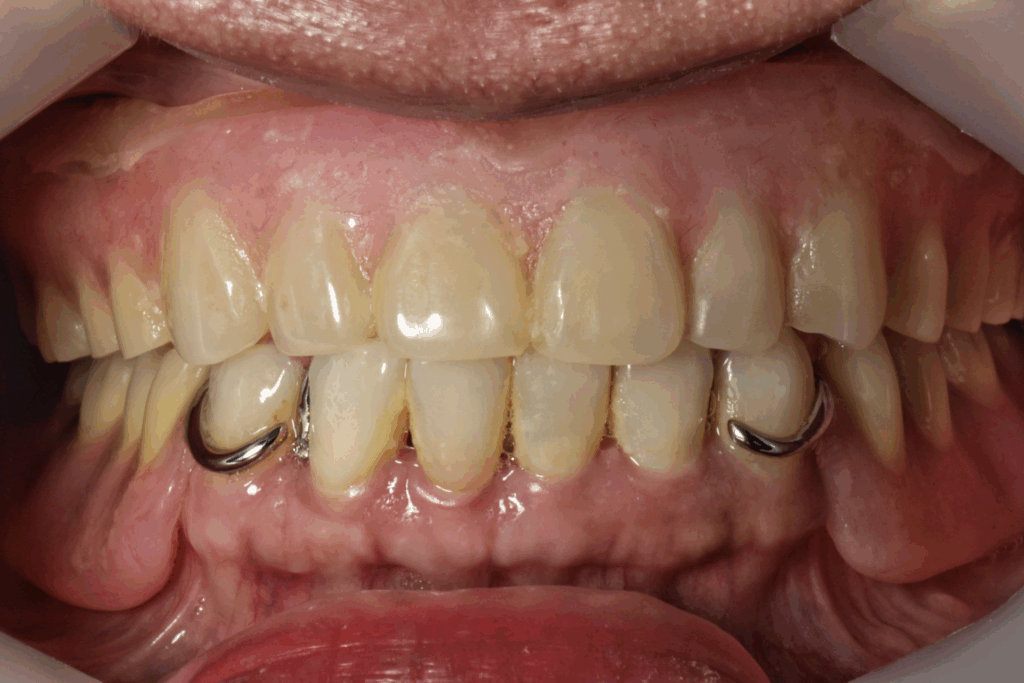

案例2. 上顎+下顎All on X

Before

After